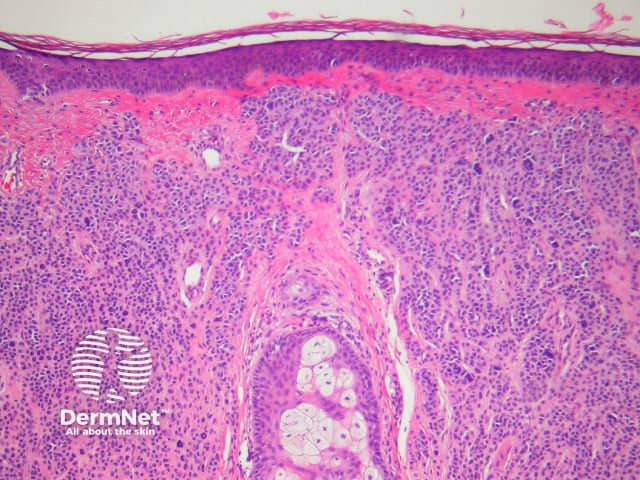

Typical pathological features of chronic plaque psoriasis are:

Pathology of psoriasis x40

Pathology of psoriasis x200